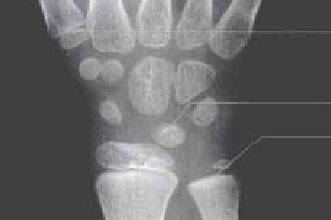

腕骨骨化中心出现的时间

头钩三角月

舟大小豌豆